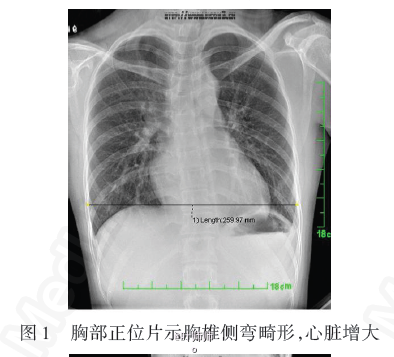

患者,女性,24岁,主因间断胸闷、心悸数月就诊. 5岁时曾因外伤导致胸骨塌陷。

查体发现患者消瘦,身高170cm,体重仅41kg,胸廓前后径明显缩短,胸骨明显凹陷呈漏斗状。 心脏彩色多普勒:左心室流出道血流速度偏快,不除外胸廓压迫所致。 动态心电图:窦性心律(部分时段出现多源性异位房性心律);室性早搏(3个),室上性早搏(181个),部分出现阵发性室上性心动过速,电轴右偏。

诊断:直背综合征